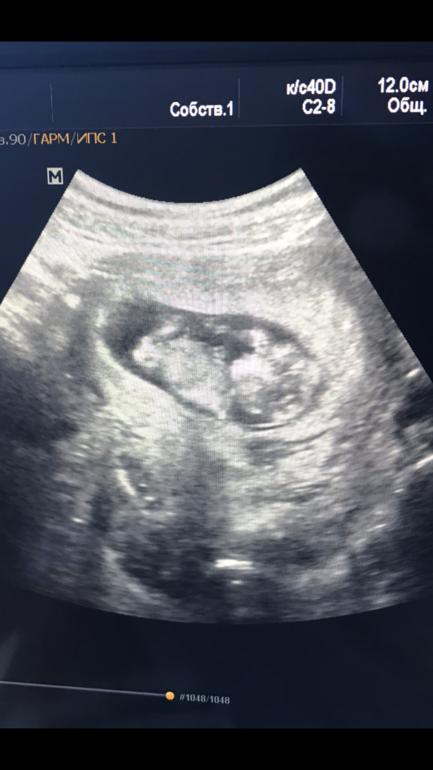

Рядом ножка и бугорок , второй ножки не видно.Вот фото сына

Вот фото 12 недель и 3 дня. 1 скриннинг у генетика. Пол правда тогда никто не сказал и не пытался предположить. Уже потом узнали, что это мальчишка